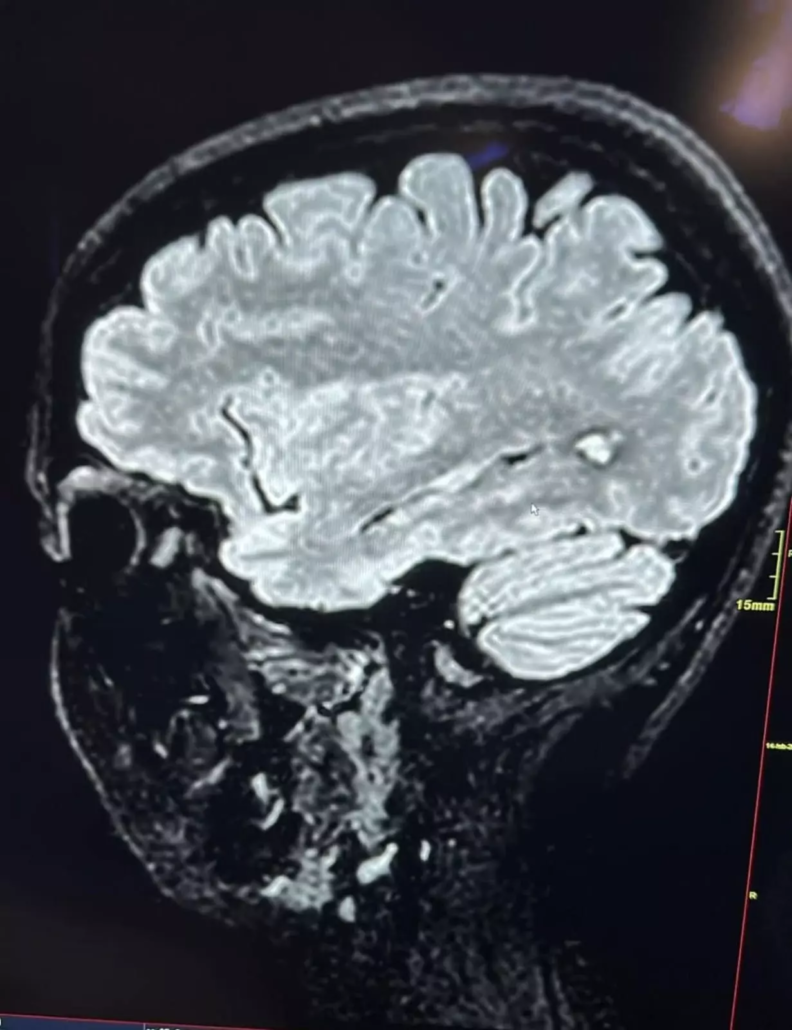

La paziente lamentava acufene pulsante, ovattamento auricolare, senso di pressione all’orecchio e perdita dell’udito. Al quadro clinico si associavano marcati sintomi psicologici: ansia crescente, difficoltà di concentrazione e sintomi depressivi. Dopo aver consultato diversi specialisti senza ricevere una diagnosi precisa, la paziente si sentiva smarrita e priva di speranza. Sin dalla prima visita, abbiamo sospettato una componente vascolare alla base della sintomatologia. Gli esami audiologici eseguiti in sede hanno rafforzato la nostra ipotesi, portandoci a richiedere con urgenza esami radiologici approfonditi: risonanza magnetica dell’encefalo, valutazione dell’articolazione temporo-mandibolare e studio dei distretti vascolari cerebrali. I risultati non hanno lasciato dubbi: la paziente era affetta da un angioma cavernoso encefalico di circa 10 mm, già sanguinante, con deposito di emosiderina come segno di precedenti microemorragie.

L’angioma cavernoso, noto anche come cavernoma, è una malformazione vascolare benigna del cervello, costituita da un intreccio anomalo di vasi capillari dilatati con pareti sottili. Può essere congenito o acquisito e si manifesta con una varietà di sintomi neurologici, oppure può restare silente per anni. Quando sintomatico, l’angioma cavernoso può causare emorragia cerebrale, crisi epilettiche, cefalea persistente, acufene, ipoacusia, vertigini, disturbi cognitivi e alterazioni dell’umore. Nel caso specifico della paziente, l’angioma era localizzato in una zona encefalica delicata e già soggetta a sanguinamento. Il rischio di un’emorragia cerebrale massiva era alto. Dopo la diagnosi, abbiamo immediatamente avviato una consulenza neurochirurgica. Il collega neurochirurgo ha confermato l’indicazione all’intervento di asportazione chirurgica dell’angioma per prevenire ulteriori sanguinamenti e possibili danni irreversibili.